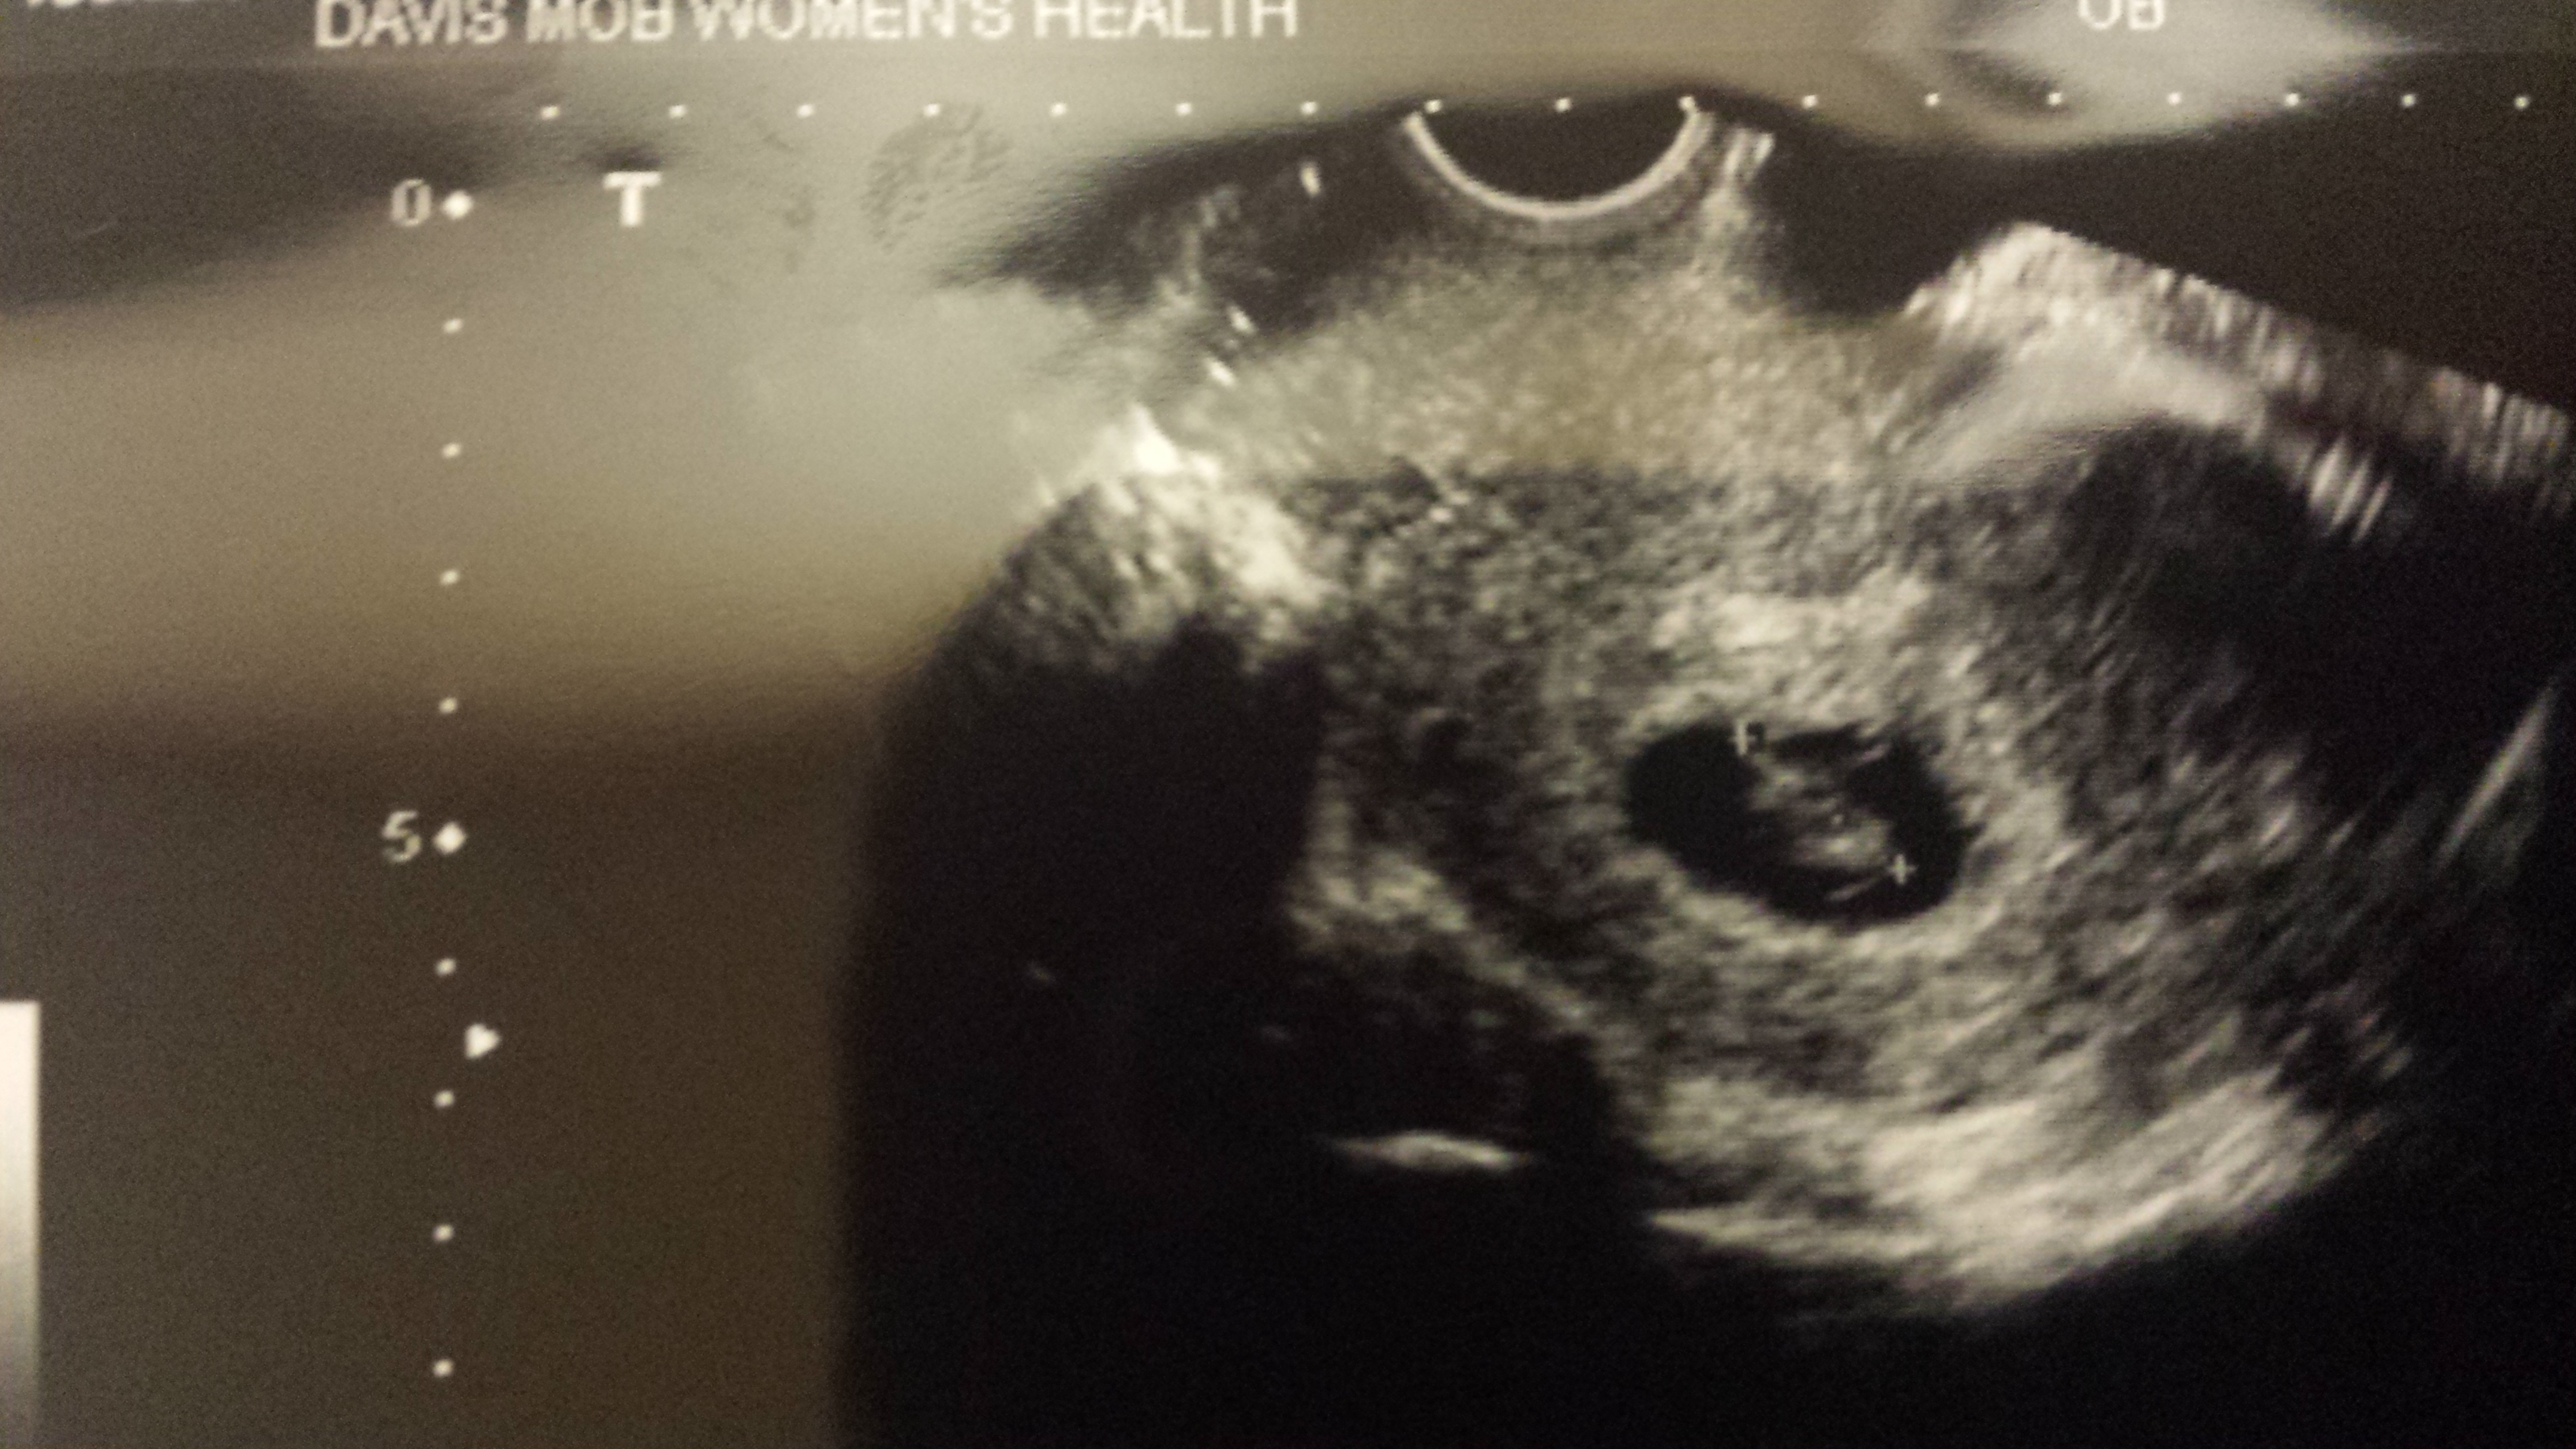

Take at 8 weeks gestation. Transvaginal

I honestly have no idea how this theory works...I don't put a lot of trust in it but figured it doesn't hurt to have fun. All of the pictures I have seen show the embryo close to either left or right side and mine is right in the middle. Lol. Go figure.